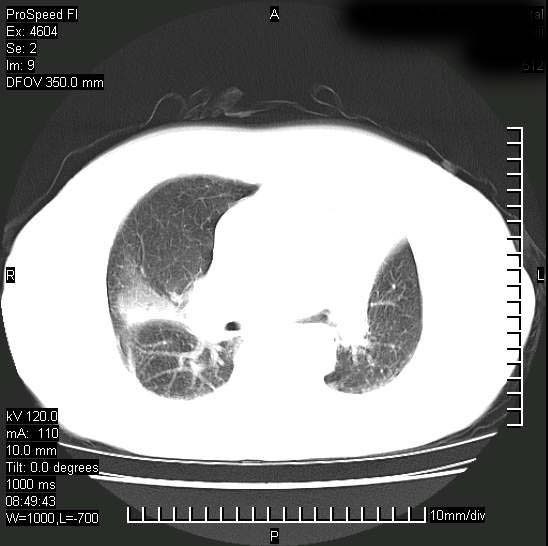

标题: CT15528:女性,79岁,近几日晚上高热,39度,仍咳少量血

十几年前曾患肺结核,一周前突咳血约100ml,中性粒细胞稍高,诊断两上肺陈旧结核,下肺炎症,给予抗炎治疗,近几日晚上高热,39度,仍咳少量血,4天前ct及今天ct上传。

[face=黑体]8月30日[/face]